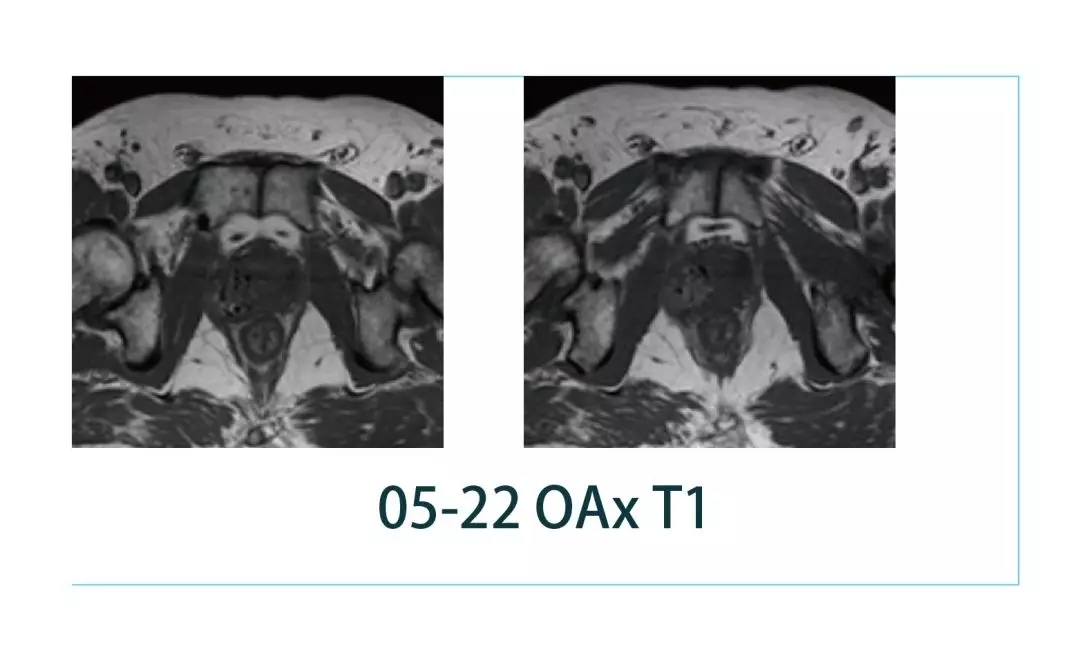

【朗润影像档案】20190322磁共振影像病例结果讨论

【朗润影像档案】磁共振影像病例分享(编号20190322)